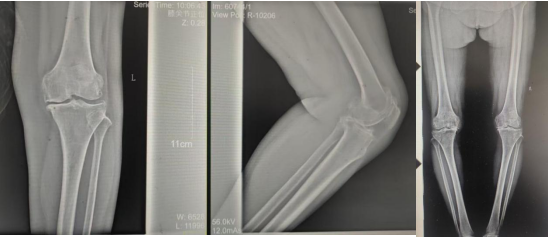

術(shù)前影像資料

張女士于10年前勞累后左膝疼痛,干活后疼痛較重,陰雨天及受涼時(shí)疼痛明顯,行走時(shí)可聞及關(guān)節(jié)內(nèi)異響,時(shí)有“打軟腿”現(xiàn)象,曾到附近多家醫(yī)院診治,給予膝關(guān)節(jié)針灸、膏藥外貼、口服藥物等“保守”治療,治療后疼痛癥狀略有好轉(zhuǎn),但易復(fù)發(fā);近2年患者左膝關(guān)節(jié)疼痛逐漸加重,行走跛行,下蹲及上下樓梯困難,活動(dòng)時(shí)疼痛明顯,休息、保守治療后疼痛無明顯好轉(zhuǎn)。

張女士的鄰居看她上下樓如此困難,日常生活都很受影響,因其以前在我院看過腰椎,效果良好,故介紹張女士來我院找萬昌勝主治醫(yī)師進(jìn)行咨詢問診。萬醫(yī)生了解情況后帶她到我院關(guān)節(jié)外科進(jìn)行更專業(yè)的診治。關(guān)節(jié)外科門診醫(yī)師結(jié)合癥狀體征及影像學(xué)檢查,建議入院手術(shù)治療,以“左膝骨性關(guān)節(jié)炎伴膝內(nèi)翻、高血壓病”收住入院。